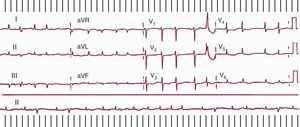

Aleteo auricular típicoEl AA típico es la TAMR más frecuente, y en general se puede identificar por un patrón de ECG muy característico en derivaciones inferiores que, aunque se describe frecuentemente como una onda negativa, es en realidad una ondulación compleja con una fase descendente lenta, seguida de un pequeño descenso rápido (la «onda negativa») y un rápido ascenso que termina en una deflexión positiva, para enlazar de nuevo con el descenso lento del ciclo siguiente (Figura 1, Figura 3, Figura 10). En V1 se pueden registrar deflexiones positivas, bifásicas o a veces negativas.

Figura 10. A la izquierda electrocardiograma en 2 casos de aleteo auricular típico (antihorario), con las típicas ondas multifásicas en II, III y aVF y con deflexiones bifásica y positiva en V1. A la derecha, 2 casos de aleteo auricular típico inverso (horario), con ondas de aspecto positivo en II, III y aVF y el típico patrón de W en V1 (véase el texto para más explicación). AA: aleteo auricular.

En un 90% de los casos, el giro de la activación en el circuito de AA típico es antihorario en una visión oblicua anterior izquierda (descendiendo la AD anterior y ascendiendo la septal). Esta preferencia podría deberse a una mayor facilidad para el bloqueo de la conducción descendente en la AD septal baja, donde el miocardio es de muy escaso grosor y alineamiento irregular. Si una extrasístole se bloquea a este nivel, la conducción del frente de activación descendente por la cara anterior podría reentrar la AD septal a través del istmo cavotricuspídeo (ICT), y así se inicia el giro antihorario. El AA típico inverso (horario) recorre el mismo circuito descendiendo la AD septal y ascendiendo por la AD anterolateral, con la misma línea de bloqueo en la AD posterolateral y el mismo cierre inferior a través de ICT (Figura 7, Figura 10). El patrón de ECG es distinto del AA antihorario, con inscripción en cara inferior de deflexiones positivas melladas en forma de M y en V1 de onda negativa, ancha, mellada en forma de W (Figura 10).

Cuando el ECG registra una taquicardia a > 240 lpm con un patrón típico de AA antihorario u horario (ya comentado) y bloqueo AV fijo o variable, en un paciente con o sin cardiopatía orgánica, sin antecedentes de cirugía cardiaca, el diagnóstico de AA típico dependiente del ICT es casi seguro. Si la morfología de las ondas no se aprecia bien, se puede aumentar el grado de bloqueo AV con masaje carotídeo o con la inyección de ATP o adenosina, registrando en ese momento las derivaciones de los miembros y V1. En pacientes con antecedentes de atriotomía quirúrgica el patrón ECG de AA típico deja de ser específico (Figura 14).